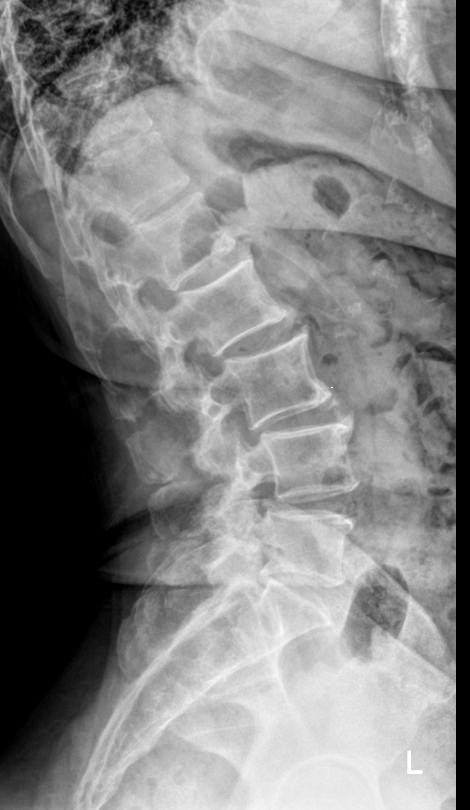

Поясничные позвонки, с 1 по 5, самые крупные во всем позвоночнике, так как удерживают большой груз ― всю верхнюю половину тела. Это последние отдельные позвонки, следующие 5 крестцовых позвонков срастаются в единую крестцовую кость. Благодаря массивности поясничный отдел может выдержать довольно сильные удары, однако травмы наблюдаются и в этом месте. Но большая часть патологий поясницы вызвана хроническими дегенеративно-дистрофическими изменениями. И чаще всего они развиваются в пояснично-крестцовом сочленении.Увидеть произошедшие с позвоночником изменения позволяет рентгенография. На снимке обычно видны все 5 поясничных, 12-й грудной и 1-й крестцовый позвонки. В некоторых случаях врачу необходим обзор крестца до уровня 3-4 позвонков. Снимки выполняются всегда в 2 проекциях.

Что покажет рентген поясничного-крестцового отдела позвоночника

• Сохранение или изменение поясничного лордоза;

• Признаки сколиоза: искривление оси позвоночника, в какую сторону, на сколько градусов, на уровне какого позвонка, с ротацией или без;

• Признаки нестабильности в поясничном отделе позвоночника

• Изменение высоты тел позвонков и межпозвонковых дисков ;

• Дистрофические изменения тел позвонков, костные разрастания, склероз;

• Наличие грыж Шморля;

• Травматические повреждения;

• Новообразования.

• Боковая ― строго боком к пластине, убрав руки за голову;